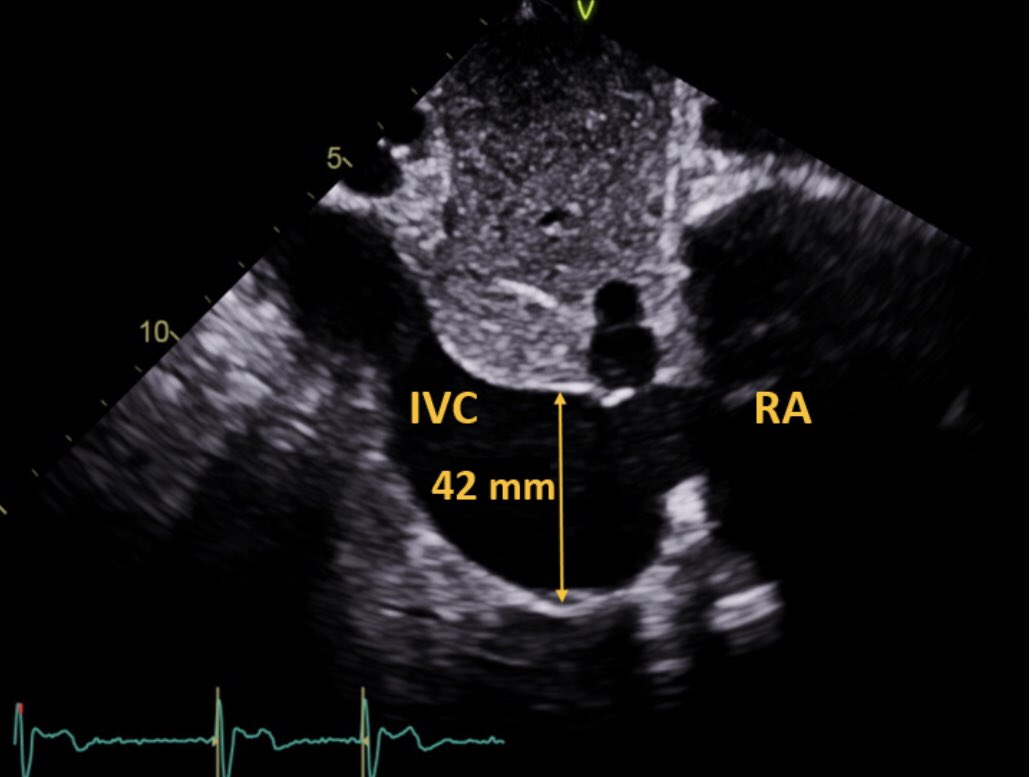

2/6 In certain cases such as this one IVC assumed aneurysmal. IVC aneurysm is defined as 40 mm or greater (reference below) .... #echofirst

3/6 This patient with severe TR (note TR jet entering into IVC) as demonstrated has an aneurysmal dilation of the IVC at the atrial-caval junction measuring 42 mm... #echofirst